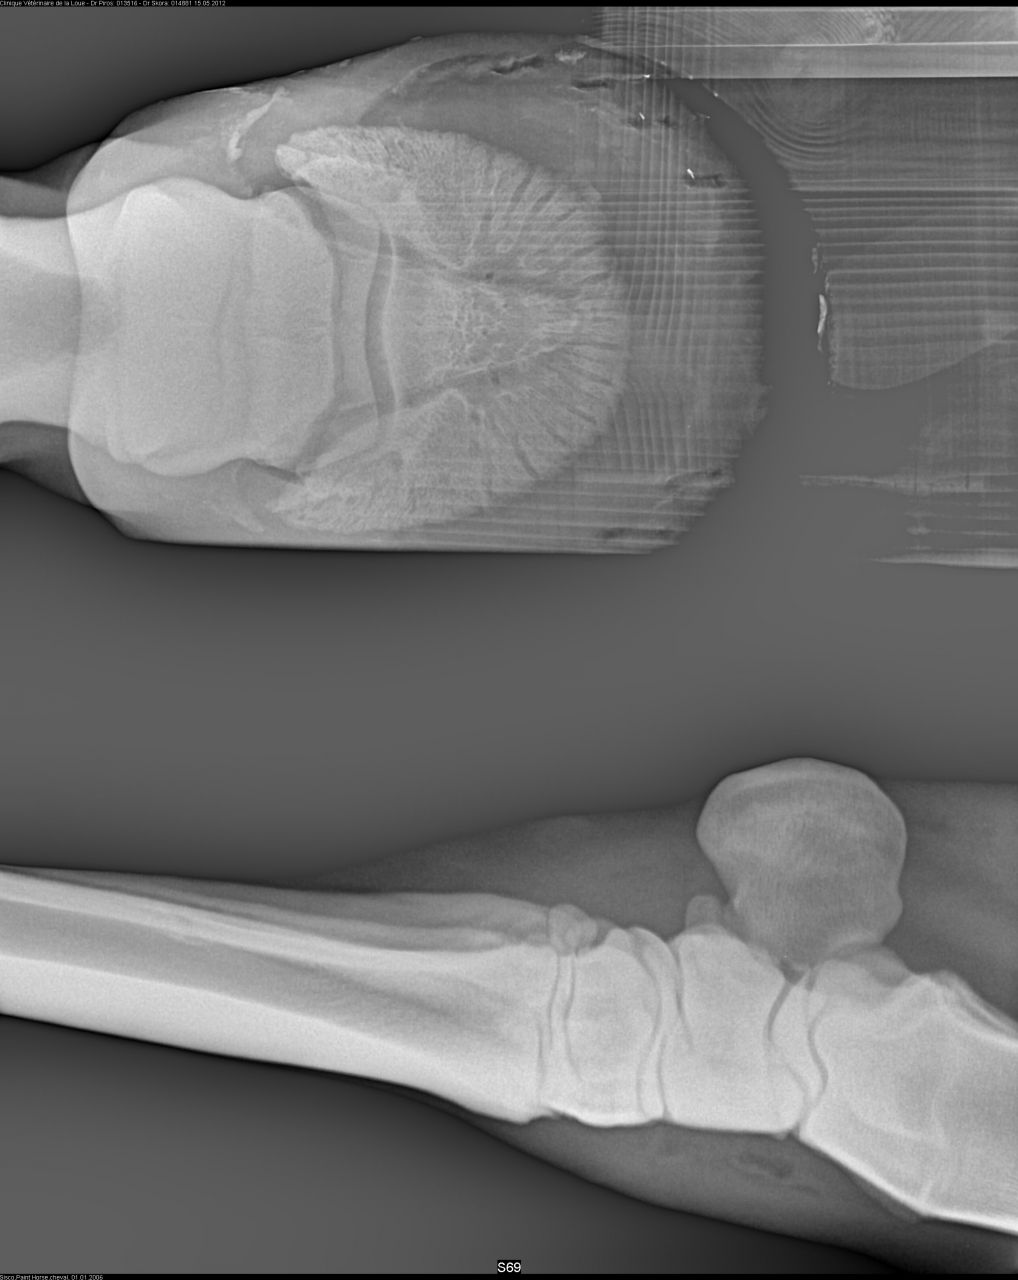

| Dire merci | ![]() voici les radios du pied droit Si quelqu'un si connait et y verrait une anomalie. Le véto m'a dit que tout était ok. |

| Dire merci | de toute façon parage naturel ou non j'aurais eu ce soucis, peut être un an plus tard voir plus... Ca a juste accélérer le problème. Il a en plus une ostéite. Sinon le véto a fait exactement ce que mon véto a fait... Sauf qu'il a un oeil d'expert et pas de généraliste. Pour la "tendinite", (le tendon frottait un os qui pour finir l' abrasait ) qui est du au talon bas. Don on a fait 4 radios du pieds. On lui donne un anti inflammatoire pendant une semaine. Il a des fers à l'envers aux antérieurs. Et 6 mois de box avec sorti de 10 min par jour pendant un mois puis on rallonge de 5 min chaque semaine... Je retourne à la clinique fin septembre début octobre. |

| Dire merci | ![]() ![]() c'est le pied gauche ![]() le pied droit |